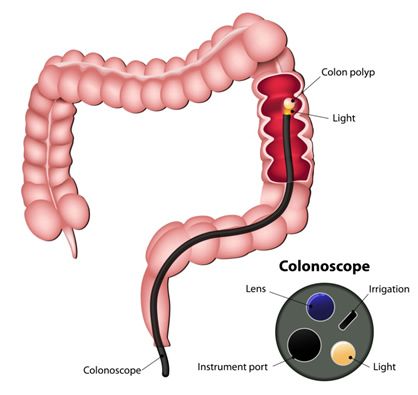

Η κολονοσκόπηση επιτρέπει την εκτίμηση της έκτασης του όγκου και τη διενέργεια βιοψίας για την επιβεβαίωση της διάγνωσης (Εικόνες 9, 10).

Ο πλήρης κολονοσκοπικός έλεγχος είναι απαραίτητος, διότι επισυμβαίνουν σύγχρονοι όγκοι.

Εικόνα 9.

Κολονοσκόπηση

Σύγχρονοι καρκίνοι στο παχύ έντερο υπάρχουν σε ποσοστό 2-8%, ενώ πολύποδες συνυπάρχουν σε άλλα σημεία του παχέος εντέρου εκτός του κακοήθους νεοπλάσματος σε 20-30%.